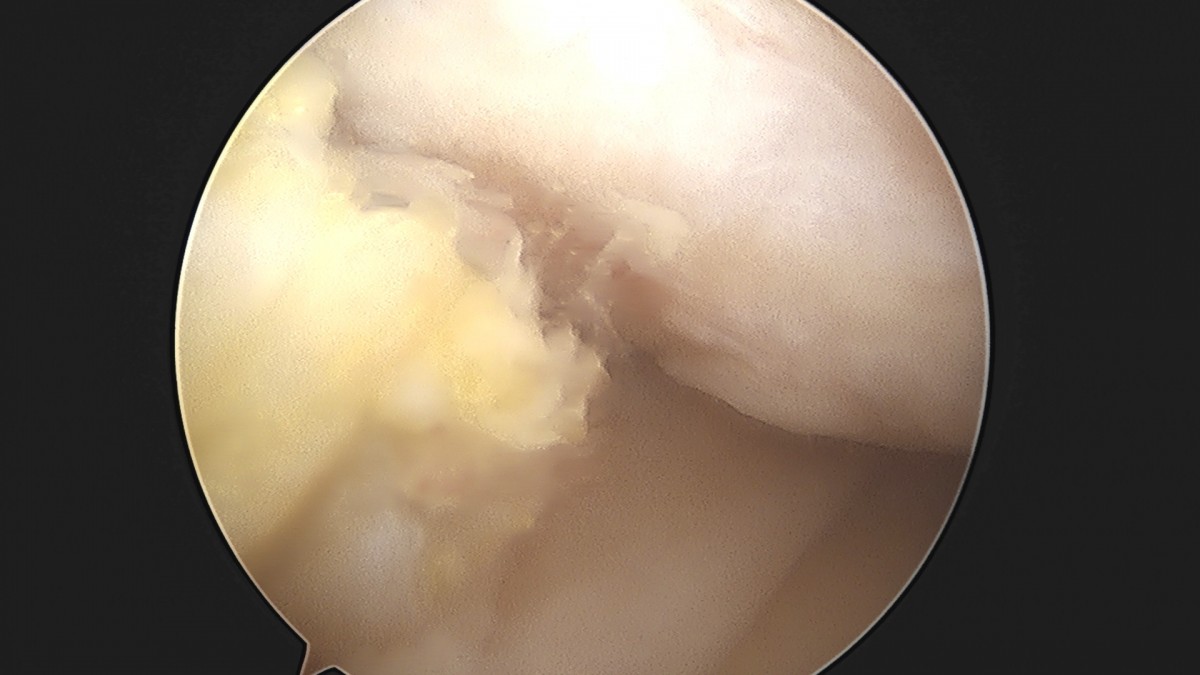

이재상원장님 무릎 반월상 연골판 절제술 김민O 환자

작성자 최고관리자 댓글 0건 조회 365회 작성일 25-09-16 16:10